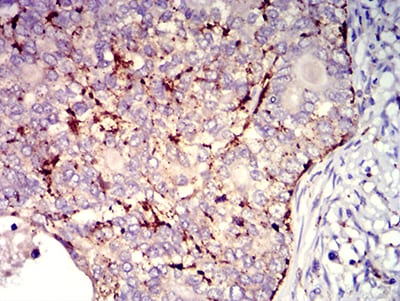

Product Image |

| IHC | 1/200 - 1/1000 |